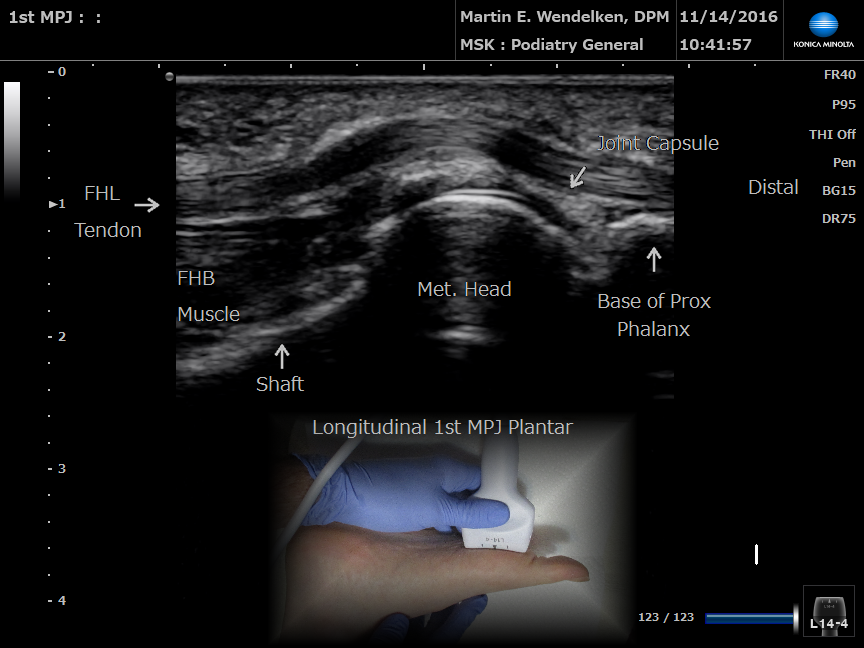

• Image 1: 1st Metatarsal Phalangeal Joint